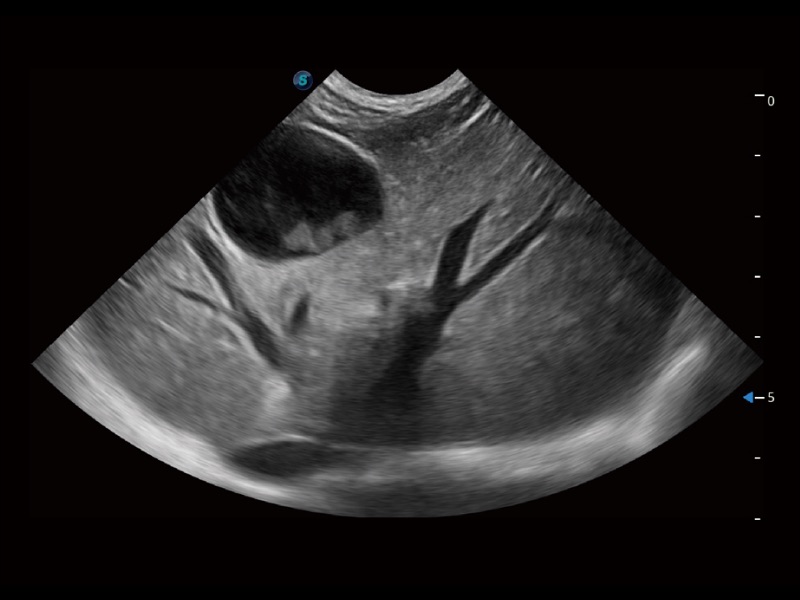

大型犬、马科、农场动物及大型异宠动物

一键自动识别膀胱壁及自动测量膀胱容积,不受膀胱形状和大小的限制,帮助医生快速精准获得测量的数据。

通过360度任意调节3条M型取样线,在同一心动周期上观察心脏不同位置的运动曲线,得到准确的心功能测量数据,有效评估心肌运动及左心室功能。